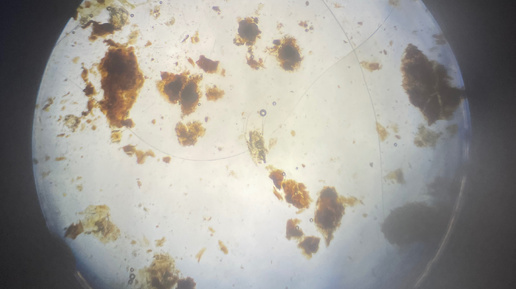

Отодектоз (ушная чесотка) – это заразное заболевание, вызванное микроскопическими клещами Otodectes cynotis. Эти паразиты живут в ушных каналах собаки, питаясь кожными выделениями и вызывая сильное воспаление. Без лечения отодектоз может привести к серьезным осложнениям, включая отит и даже потерю слуха. Клещи передаются: ✔ При контакте с больным животным(кошками, собаками). ✔ Через общие предметы ухода(подстилки, расчески). ✔ От матери к щенкам. Заподозрить ушного клеща можно по следующим признакам:...